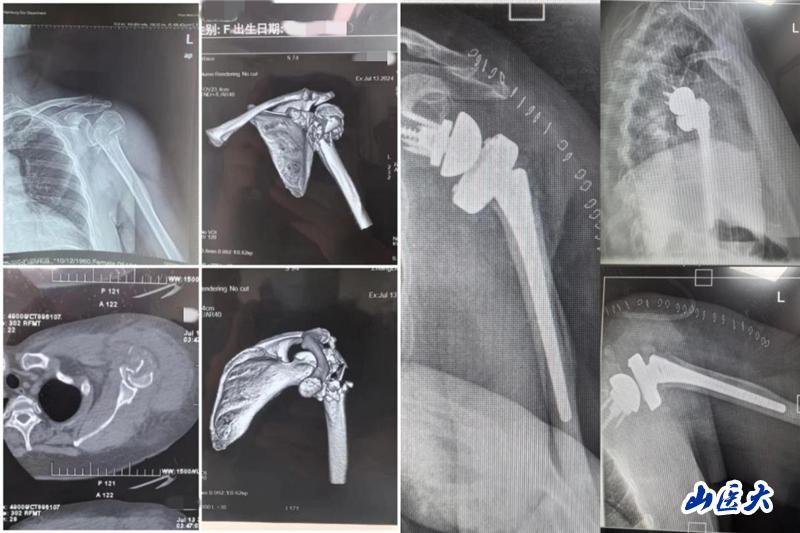

患者是一位63岁女性,主因车祸致左肩关节疼痛、肿胀伴活动受限就诊,完善相关检查结果示:左肱骨近端粉碎性骨折。栗树伟副主任医师团队多次进行术前病例讨论,综合患者年龄较大、骨折类型为严重肱骨近端粉碎性骨折、肩关节功能严重受损等因素考虑,本着最大程度提高患者生活质量的医疗服务理念,决定为患者实施反向肩关节置换术。

经过积极充分的术前准备后,手术如期进行。由栗树伟主刀,在骨科张晨医师、麻醉科徐文会副主任医师、手术室护士高君君和张文杰等团队成员的通力配合下,凭借精准的解剖定位和精细的操作手法,最终顺利完成这台历经3小时的手术。术中患者各项指标平稳,术后安返病房。

术后的精心护理对患者的恢复也至关重要,护理团队耐心、细心、用心地护理和交流让患者充分感受到关爱与温暖。目前,患者术后拍片假体安置满意,切口愈合佳,肩关节功能恢复良好,现已顺利出院。